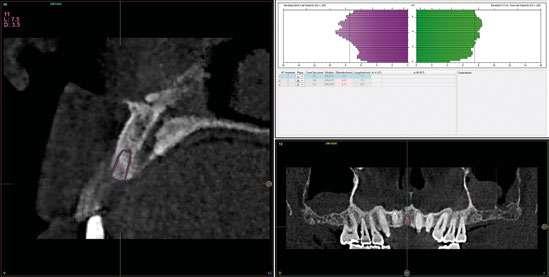

laterales se ponen de manifiesto aún más varias lesiones de esmalte que indican la parafunción en el paciente, unido a los desgastes excesivos en varias zonas (figuras 3 y 4). El paciente acude por dolor y movilidad en la pieza 11, que se ha incrementado en los últimos días, además de sensación de “diente crecido” que como podemos ver en las fotografías iniciales es real, ya que el diente se encuentra ligeramente extruido en relación con el contralateral. Estos signos parecen indicarnos una fractura o fisura. En la fotografía oclusal, podemos observar el desplazamiento del diente debido a la movilidad (figura 5). Posteriormente se realiza un sondaje positivo de la pieza, que lleva a 11 mm por lo que se confirma la sospecha de fractura y se procede a la exodoncia del diente, realizándose una regeneración posterior del alveolo con PRGF-Endoret y

esperándose 4 semanas hasta el cierre de los tejidos blandos y la neoformación ósea inicial para la colocación de un implante temprano. Cuatro semanas después, realizamos un cone-beam de control para conocer el estado del tejido óseo y poder planificar el implante. En el corte seccional observamos que se ha regenerado por completo el lecho receptor y tenemos un hueso óptimo para la inserción del implante, que por el tiempo transcurrido además es muy sencillo de expandir, con el propio implante generándose una expansión atraumática que nos permitirá ganar anchura ósea y con un implante estrecho de 3,5 mm de diámetro logramos posicionarlo sin dañar la desembocadura del nervio incisivo (figura 6). En cuanto a la longitud, con 7,5 es suficiente, no necesitándose un tamaño mayor para un correcto rendimiento biomecánico posterior.

Figura 6. Corte seccional de planificación del implante donde observamos el volumen óseo regenerado y la disposición del implante que se va a insertar por delante de la desembocadura del nervio incisivo.

Colocamos el implante generándose una ligera expansión vestibular, como mostramos en las imágenes intraoperatorias, para posteriormente ser sobrecorregido con hueso autólogo obtenido del fresado, embebido en PRGF-endoret y lograr una mayor anchura vestíbulo-lingual en la zona de colocación del im-

plante, clave para lograr una mejor estética y además un mantenimiento de los tejidos periimplantarios a largo plazo. En la fase quirúrgica colocamos además el transepitelial unitario para la realización de la carga inmediata y la colcación de un provisional atornillado horas después de la cirugía (figuras 7-14).

Cinco años después, llevamos a cabo un nuevo cone-beam y en el podemos observar la evolución del implante y de la sobre-corrección vestibular llevada a cabo en la cirugía inicial. Tanto el implante como el hueso que se ha formado a nivel vestibular fruto del injerto empleado está estable y se mantiene sin pérdida ósea asociada, tal como mostramos en los cortes del cone-beam

inicial y final a los 5 años de seguimiento (figura 19). En las imágenes intraorales tomadas en este punto del seguimiento se constata el éxito del tratamiento (figuras 20 y 21). En la radiografía periapical, observamos con mayor detalle la regeneración del tejido óseo del diente en posición 11 así como la estabilidad ósea del implante (figuras 22 y 23).

Figura 19. Imagen inicial del cone-beam y final con el implante cargado a los 5 años de seguimiento con la estabilidad del implante y del hueso generado mediante el injerto